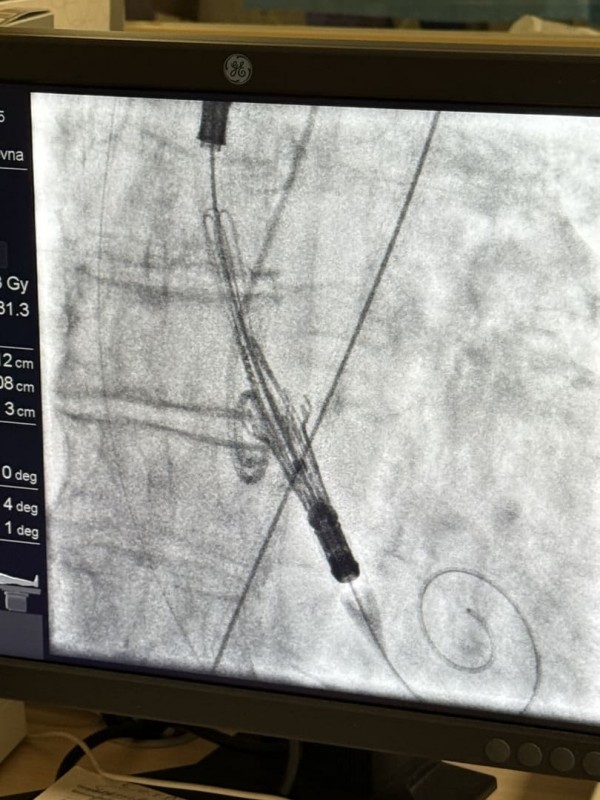

6 октября на базе нашей больницы состоялся мастер-класс по транскатетерной имплантации аортального клапана (TAVI).

В ходе мастер-класса врачи по рентгенэндоваскулярным диагностике и лечению и сердечно-сосудистые хирурги нашей больницы выполнили операции двум пациентам кардиохирургического отделения под руководством специалиста Федерального специализированного сосудистого центра Дмитрия Дмитриевича Зубарева, кандидата медицинских наук, заведующего отделением эндоваскулярной хирургии ФГБУ «НМИЦ им.В.А.Алмазова» Минздрава России.

TAVI (транскатетерное имплантирование аортального клапана) — малоинвазивный способ замены или имплантации аортального клапана без классического «открытого» вмешательства через грудную клетку.Основная идея — через сосуд (чаще всего бедренную артерию) или через минимальный доступ доставляется катетер с новым клапаном, который развёртывается на месте старого.